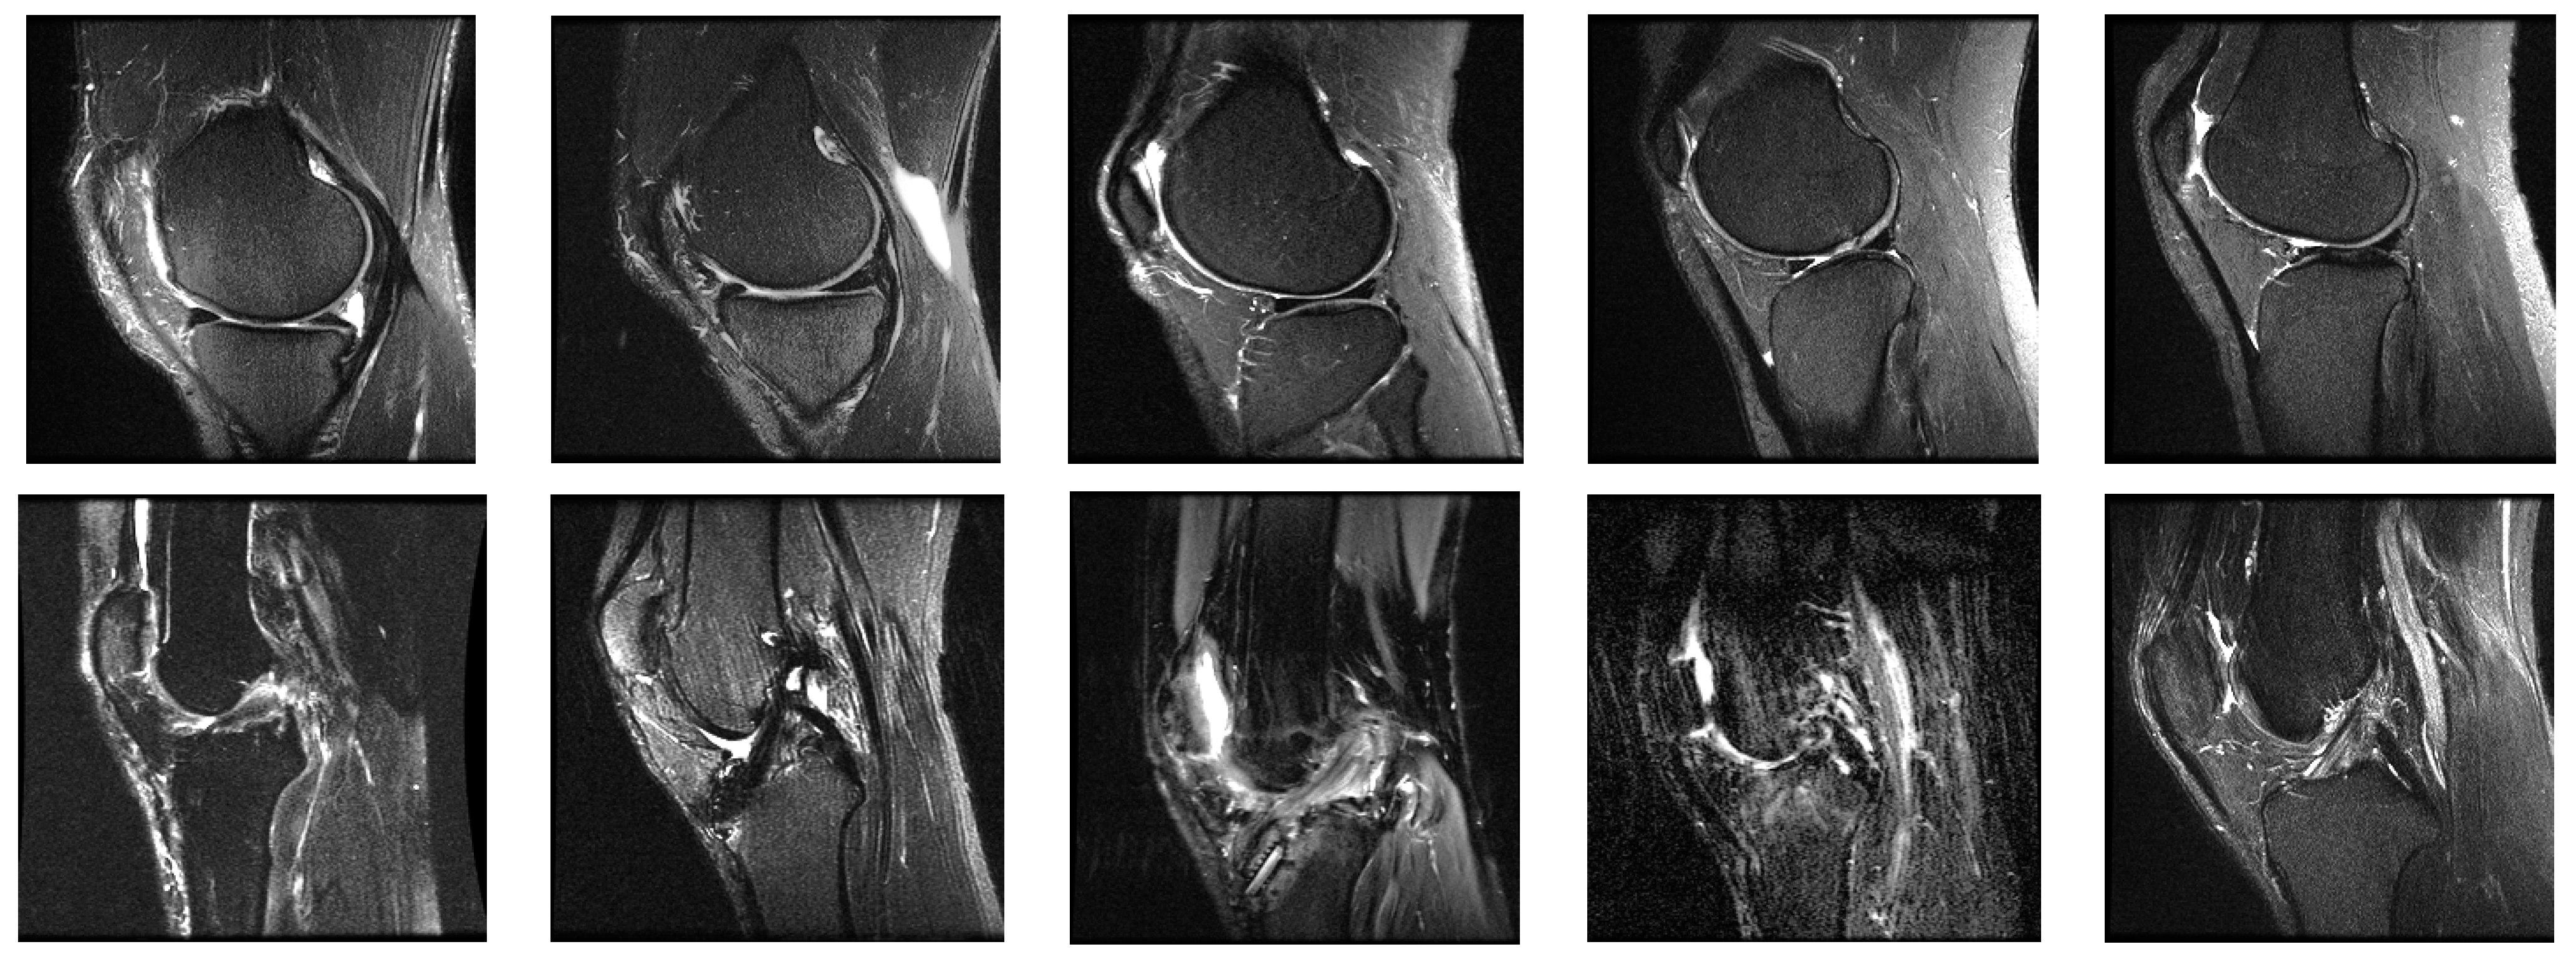

4.1. System Configurations and Dataset